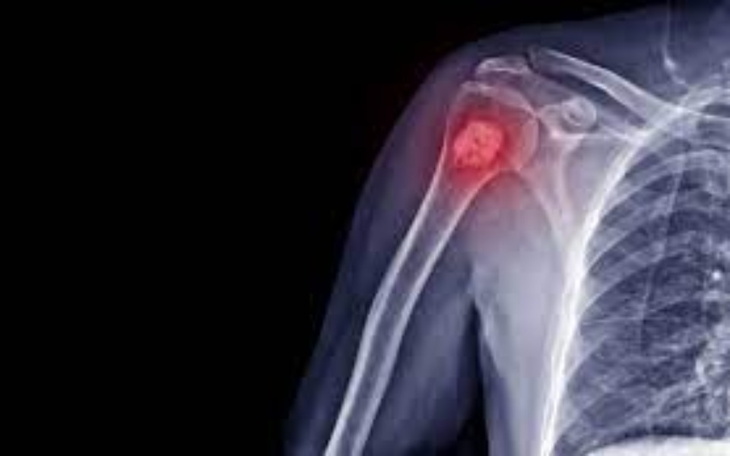

Cześć jestem Kuba i mam dziadka chorego na raka kości. Jeśli pomożecie mi uzbierać pieniążki możliwe że mój dziadek przeżyje ten horror